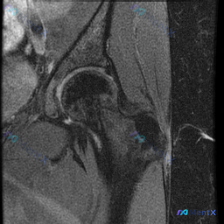

这是一张髋关节矢状位T2加权MRI图像,核心观察结果如下:

- 骨性结构:股骨头外形圆滑,无明显塌陷变形,软骨下骨板轮廓大致完整,未见骨质破坏

- 关节间隙:髋关节间隙宽度正常,关节内未见明显大量积液

- 病变区域:股骨大转子周围(臀中肌、臀小肌肌腱附着点及外侧滑囊区域)可见明显异常信号

- 大范围混杂高信号影,边界相对模糊,呈不规则分布

- 局部肌腱增粗、信号增高,提示肌腱结构完整性可能受影响

- 周围软组织间隙可见条索状、片状高信号,提示液体聚集或炎性水肿